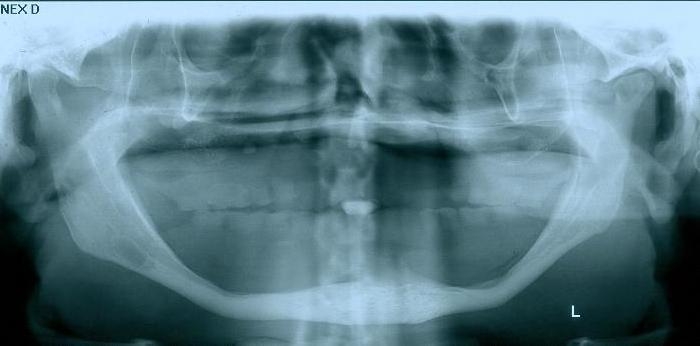

Raio - x Panorâmico inicial, em Julho de 2015